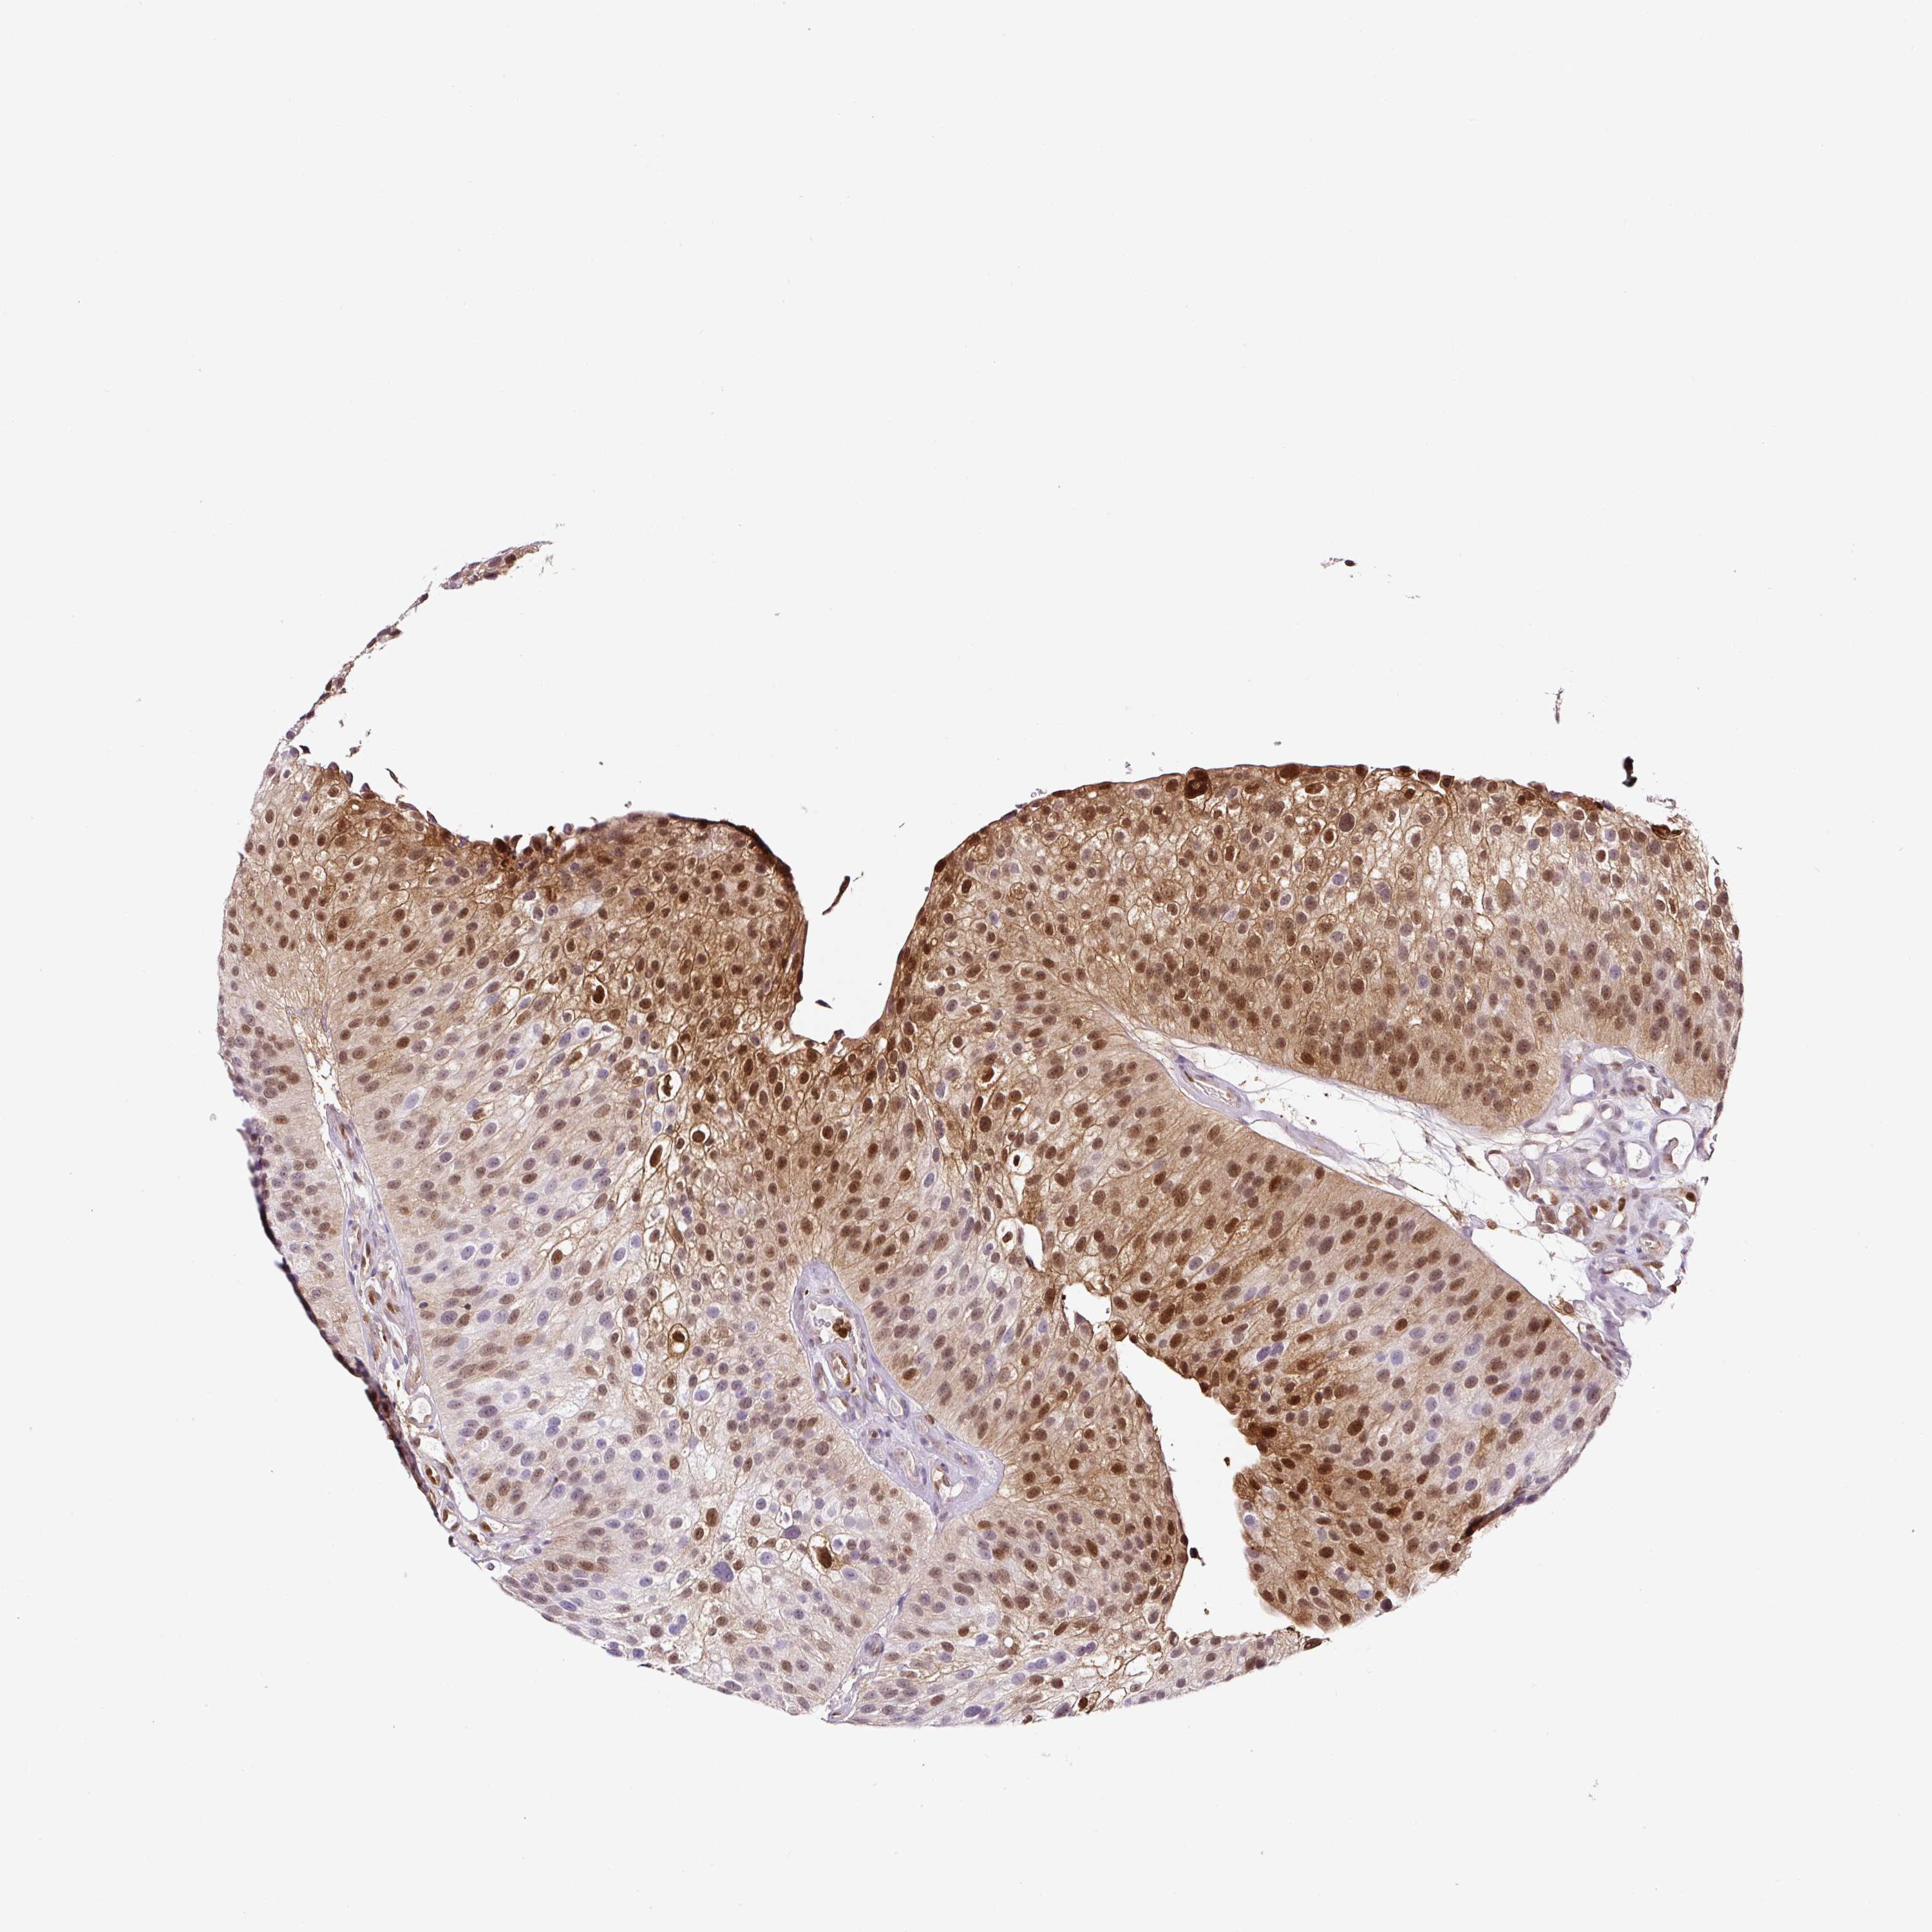

UROTHELIAL CANCER - Protein expressioni

A mouse-over function shows sample information and annotation data. Click on an image to view it in a full screen mode. Samples can be filtered based on level of antibody staining by selecting one or several of the following categories: high, medium, low and not detected. The assay and annotation is described here.

Note that samples used for immunohistochemistry by the Human Protein Atlas do not correspond to samples in the TCGA dataset.

Antibody stainingi

Antibody staining in the annotated cell types in the current human tissue is reported as not detected, low, medium, or high, based on conventional immunohistochemistry profiling in selected tissues. This score is based on the combination of the staining intensity and fraction of stained cells.

Each image is clickable and will lead to virtual microscopy that enables deeper exploration of all samples and also displays staining intensity scores, fraction scores and subcellular localization as well as patient and tissue information for each sample.

HPA011271

HPA011272

CAB013023

CAB035987

CAB058693

CAB080415

Staining

High

Medium

Low

Not detected

Intensity

Strong

Moderate

Weak

Negative

Quantity

>75%

75%-25%

<25%

None

Location

Nuclear

Cytoplasmic/membranous

Cytoplasmic/membranous,nuclear

Urothelial carcinoma, Low grade

Urothelial carcinoma, High grade

Urothelial carcinoma, NOS